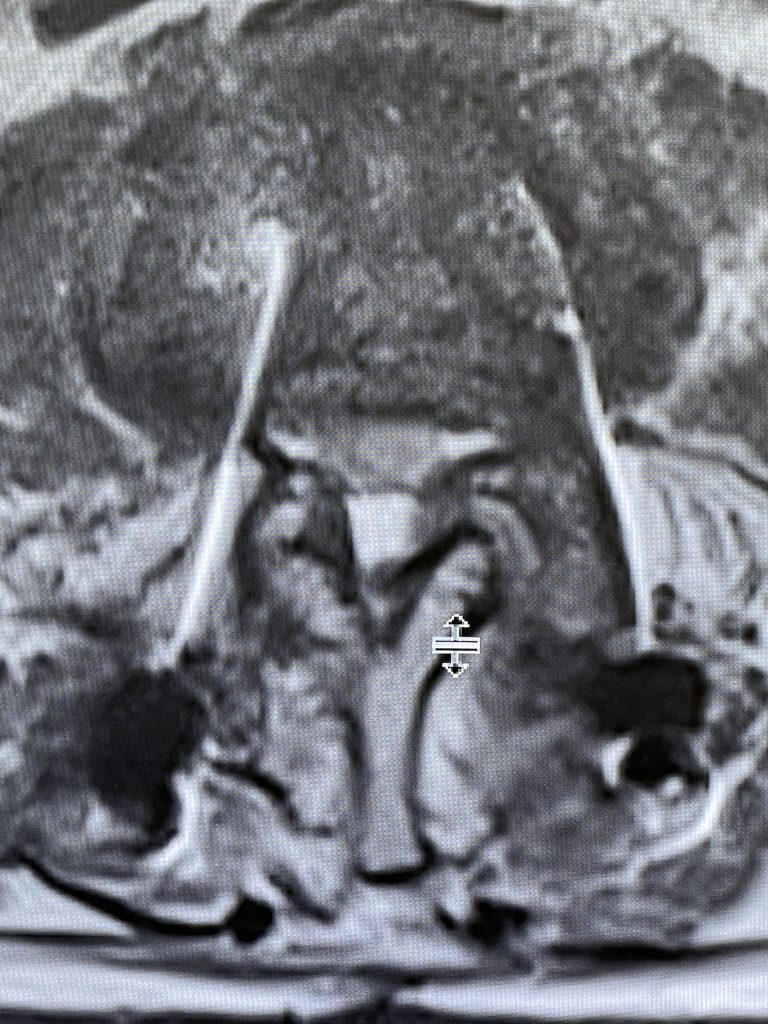

During the decompression we removed the inferior facets of L2 after the L3 screws were removed. This is a key maneuver in a revision decompression as it allows access to a dissection plane that allows the foramina and both L3 nerve roots to safely be decompressed. The L2 lamina is removed as well as a dissection plane at the inferior aspect of the bone is developed with an up biting curette. Because of her solid fusion it was only necessary to add new screws at L2 and L3 giving her a shorter construct and less potential stress at the next segment. Post operatively the patient did very well with resolution of leg pain and improved strength in her proximal leg (Figure 3).

Figure 3. Post Op AP and lateral x-rays after L2-3 instrumented fusion